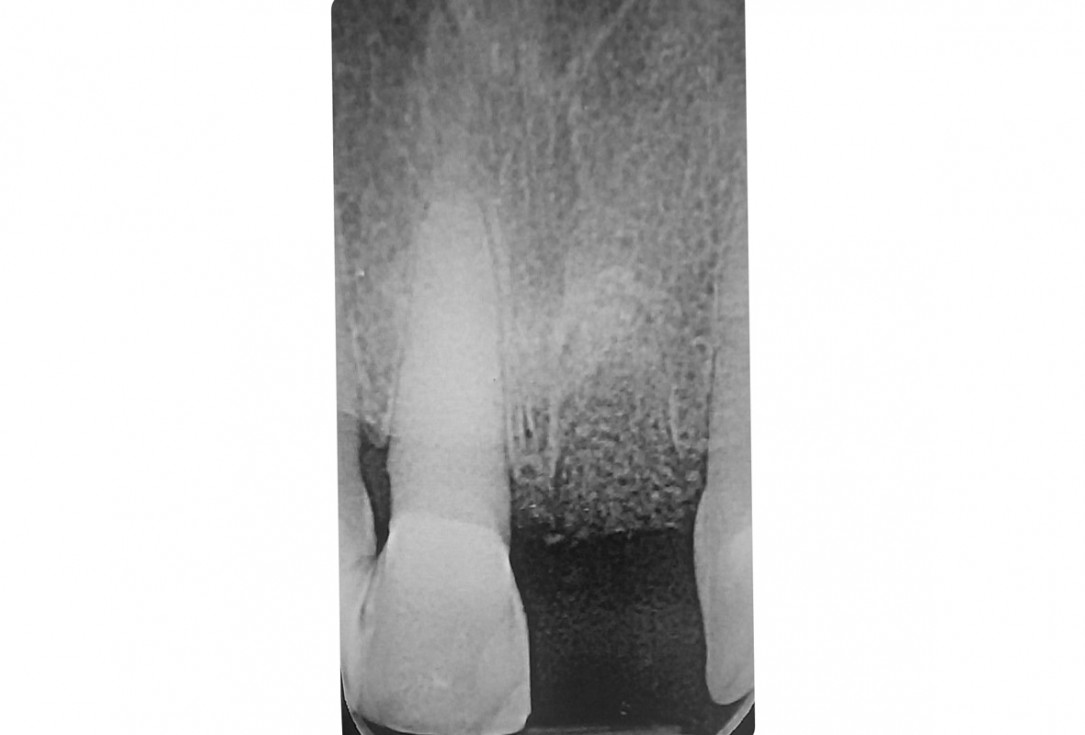

4/18 - X-ray after extractionTooth extraction and socket sealing with mucoderm® - Dr. A. Rossi